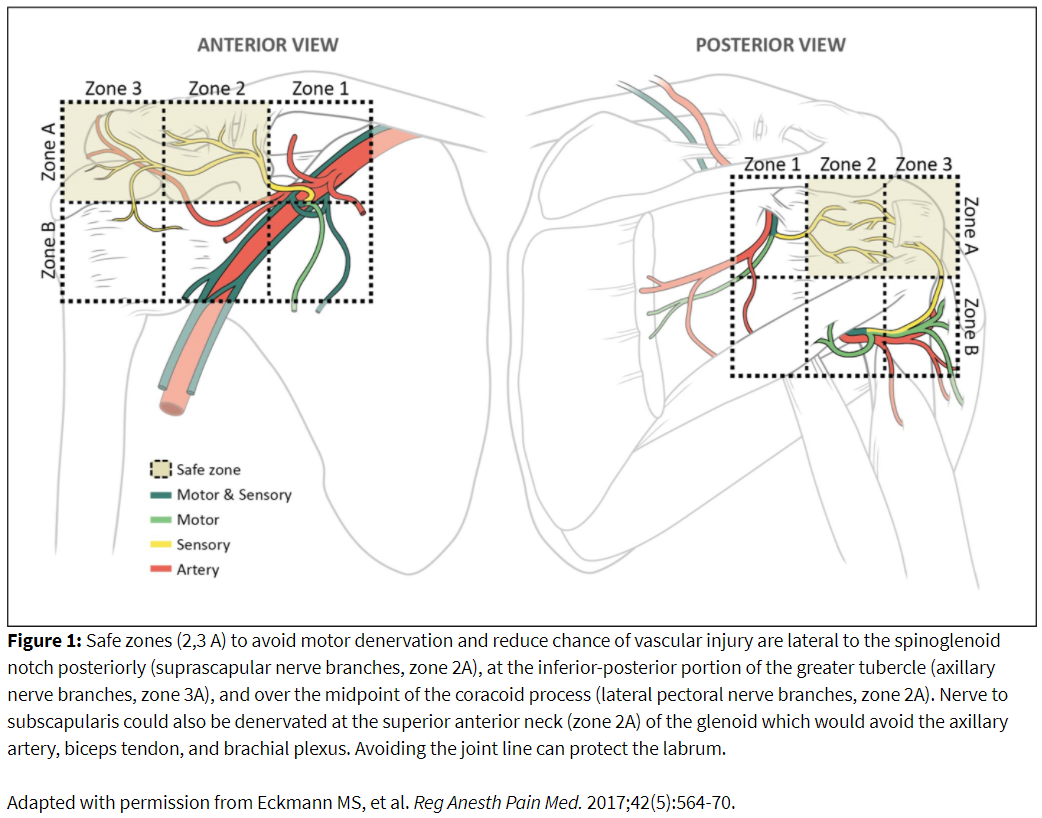

Diagnostic Block Technique: Prone Approach

An annotated image, needle placement, and ablation zone is illustrated in Figure 2. Prone positioning provides access to the posterior shoulder joint for denervation of suprascapular and axillary articular branches. The patient is positioned with the operative arm at the side to provide optimal visualization of the humerus. The image is obtained with ipsilateral obliquity to obtain the Grashey or true anterior-posterior view of the glenohumeral joint. Additional modification of this view by declining the angle caudad provides better visualization of the glenoid neck and head of the humerus along with reducing image artifact created by the spine of the scapula. The spinoglenoid notch (ie, great scapular notch) can be identified by identifying the lateral border of the scapular spine to its attachment with the neck of the scapula.

The greater tubercle appears as a step-off on the lateral head of the humerus with a tapering at its inferior margin. If the head of the humerus appears rounded, this might indicate that the tubercle is anteriorly positioned, and further oblique rotation of the image is required. An ideal view of the glenoid neck and the greater tubercle can be achieved in the same orientation, requiring no further adjustment between the two targets.

Needle depth in adults can exceed 3 inches. The needle is advanced until contact with periosteum. Contrast confirmation is recommended to exclude intravascular or intraarticular uptake. Block volume should be approximately 0.5 ml of local anesthetic.

Suprascapular articular ablation can be achieved in the top half of the posterior glenoid neck lateral to the spinoglenoid notch but medial to the joint line (Figure 2). Care should be taken not to enter the joint to reduce cartilaginous injury. The cannula will traverse the infraspinatus muscle, so care should be taken to minimize local trauma by minimizing the number of needle passes. Motor testing can be performed up to 1.5-2 volts (2 hertz). Absence of supraspinatus and infraspinatus muscle contractions should be confirmed. If there is a motor response, move the needle laterally while taking care not to traverse the labrum or joint space. Small twitches may be accepted at the discretion of the practitioner. The active tip may need to be repositioned to achieve coverage of the ablation zone. A total of 2-3 lesions can be performed in this area.

Axillary articular ablation can be performed inferior to the greater tubercle near the metaphyseal-diaphyseal junction of the humerus (Figure 2). The cannula tip will lay inferior to the distal teres minor tendon attachment. Several sensory fibers emanate from the mixed portion of the axillary nerve more medially on the posterior humeral head. Ablation in this area can increase the risk of motor denervation. Inferomedial placement close to the quadrangular space can cause trauma to the circumflex humeral artery. Absence of deltoid, teres minor, or long head of the triceps contraction should be confirmed. Positioning the active tip of the RF needle more laterally and superiorly on the head of the humerus will avoid motor recruitment. Two lesions in this area are recommended to maximize the ablation zone.